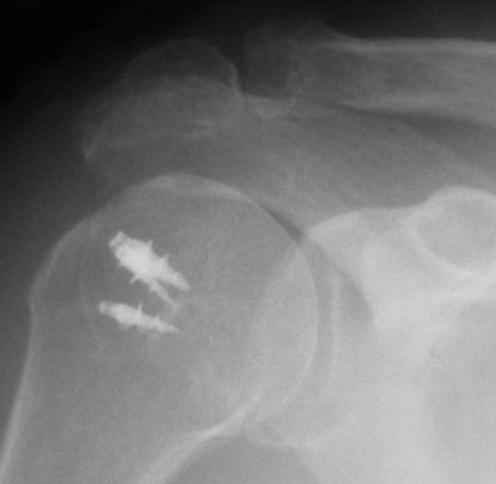

Верхний подвывих в такой ситуации может быть проявлением ротаторной артропатии, как следствия более массивного, чем частичный разрыв сухожилия надостной мыщцы, повреждения вращательной манжеты. И значит нужно думать о том, насколько полно восстановлена манжета, адекватно ли был расценен объем ее повреждения. Что за шов применялся? Якорных винтов не видно. И почему гипсовая иммобилизация? Есть прекрасные надувные отводящие подушки, позволяющие ранние движения.

В качестве примера - снимки до и после восстановления целостности вращательной манжеты после 3-хмесячной давности полного разрыва. Видно, что верхний подвывих устранен.